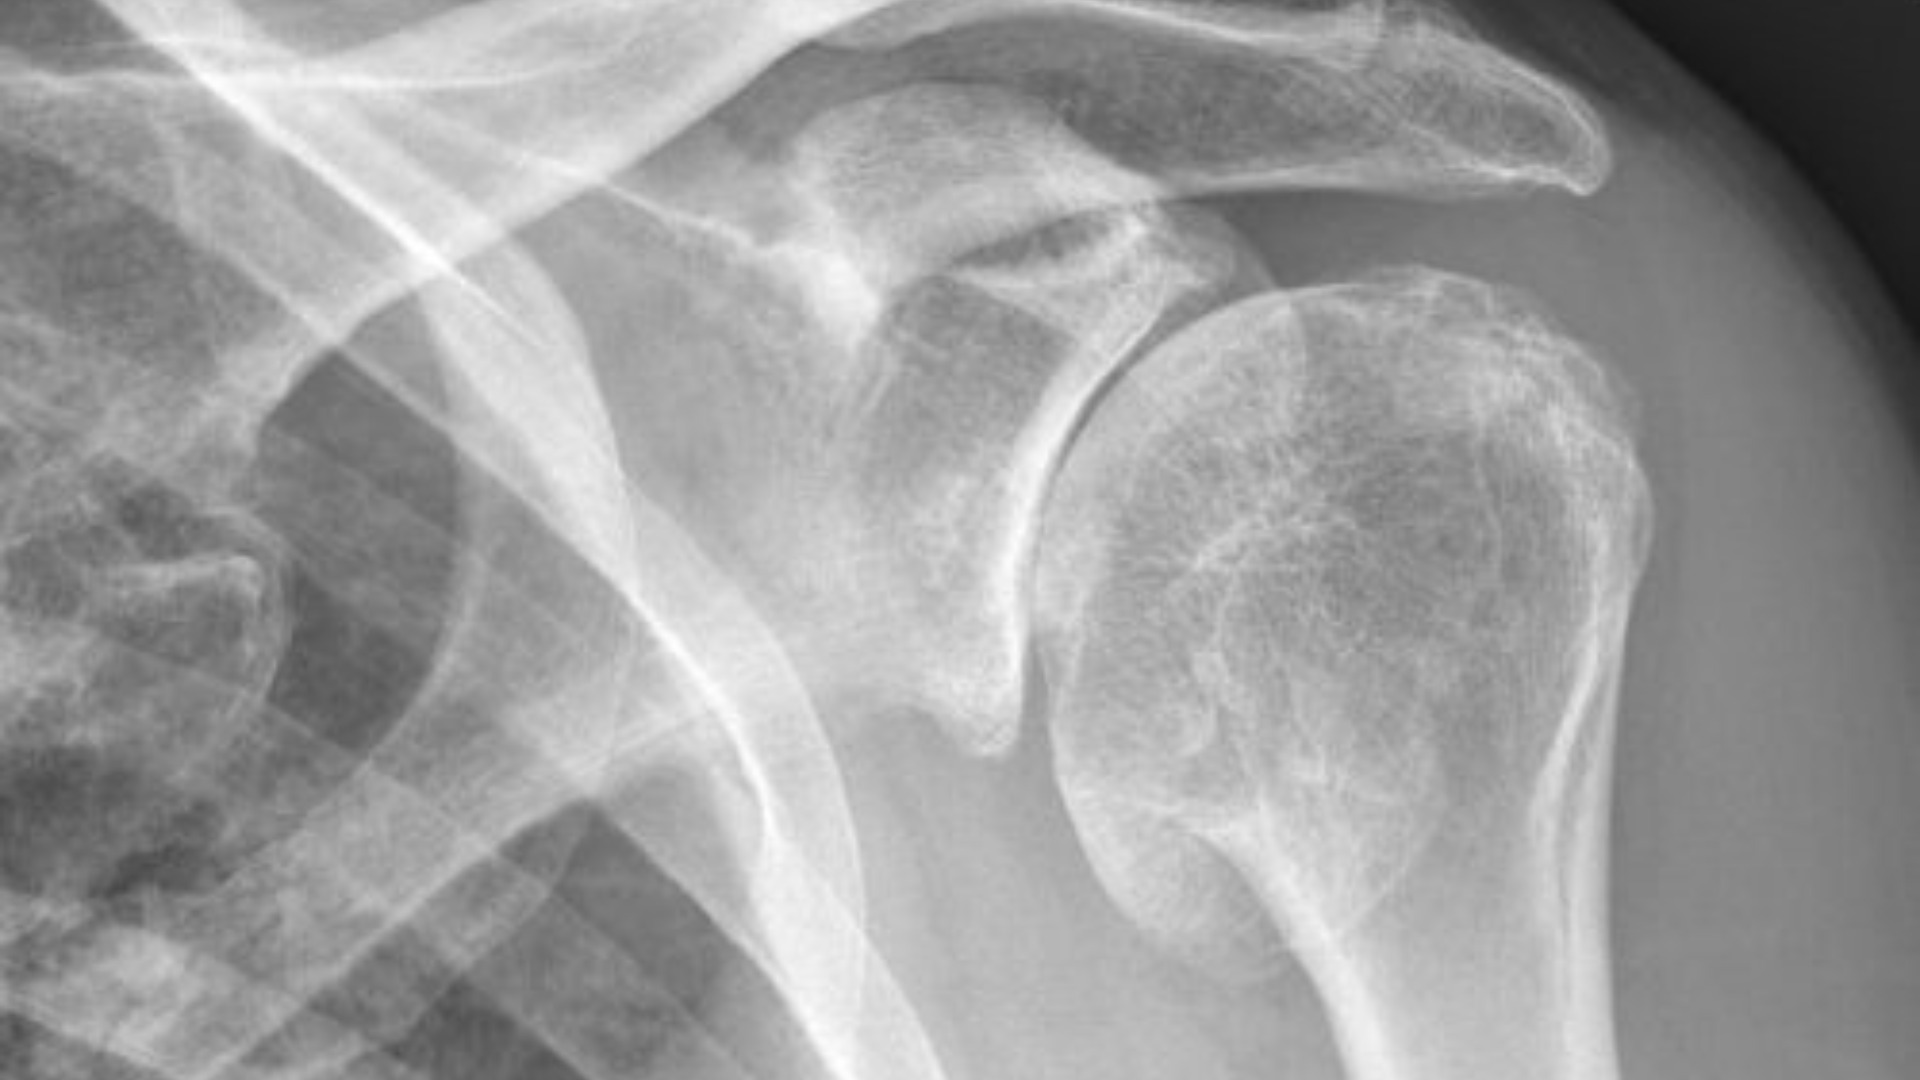

Shoulder fractures cause pain and motion loss. Miami specialists provide expert surgery, safe recovery, and restored function care…

Serious shoulder fractures cause pain and motion loss. Miami specialists provide expert surgery and structured recovery care…

Shoulder injuries can severely impact mobility, comfort, and overall quality of life. Whether caused by sports, accidents, or age-related wear and tear, shoulder damage often requires precise surgical intervention to restore strength and motion. With medical technology advancing rapidly, shoulder repair surgery in Miami has become safer, more effective, and faster to recover from than ever before.